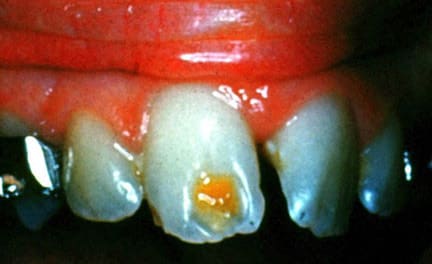

3/ HYPOPLASIE LOCALISEE POST-TRAUMATIQUE :

ASPECT CLINIQUE :

- Défaut quantitatif ponctuel de coloration jaune/brune.

- Classiquement, face vestibulaire des incisives centrales permanentes suite à impaction des incisives temporaires durant la petite enfance.